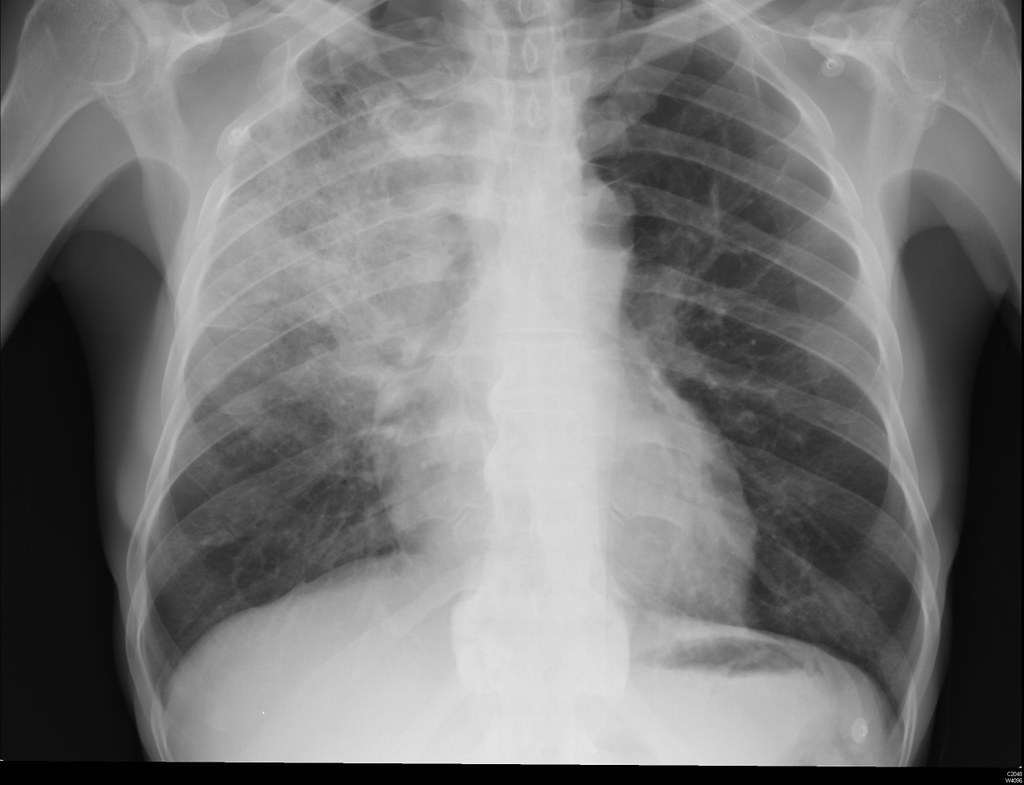

Рак на белия дроб: Ранни симптоми при 2 основни вида на заболяването

Симптоми при рак на белия дроб В повечето случаи рак на белия дроб няма симптоми в ранните си стадии. Белите дробове нямат много нервни окончания, така че туморът може да започне да своето развитие, без да причинява болка или някакви […]